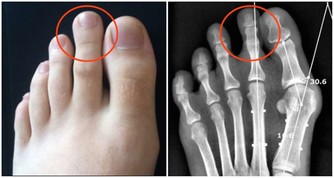

8.關節僵硬

晨僵的原因是由於在睡眠或活動減少時,使受累關節周圍組織滲液或充血水腫,

引起關節周圍肌肉組織緊張,而使關節腫痛或僵硬不適。

隨著肌肉的收縮,水腫液被淋巴管和小靜脈所吸收,晨僵隨之緩解。

可能導致晨僵的疾病包括:強直性脊柱炎、類風濕性關節炎、腰肌勞損、風濕性多肌痛、軟組織損傷、椎管狹窄等。

此外,一些過敏性病症,如多形性紅斑、皮肌炎、紅斑狼瘡、硬皮病等,也會出現明顯的晨僵現象。

因此在出現晨僵症狀後應及時到醫院就診,查明病因並及時治療。